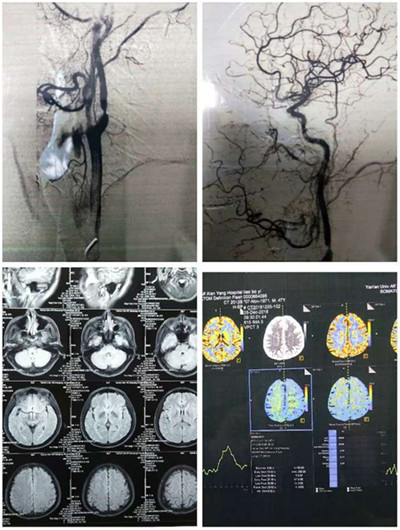

患者廖某,男,47歲,因言語不利,右側(cè)肢體活動不靈10小時入住我院神經(jīng)內(nèi)科治療,入院診斷為左側(cè)多發(fā)腦梗塞。CT顯示:左側(cè)腦室旁多發(fā)腦梗塞。B超顯示:左側(cè)頸動脈斑塊形成。為進一步明確病因,行腦血管造影,結(jié)果顯示左側(cè)頸內(nèi)動脈起始部斑塊附壁,管腔狹窄80%。

(患者檢結(jié)果1)

(患者檢查結(jié)果2)